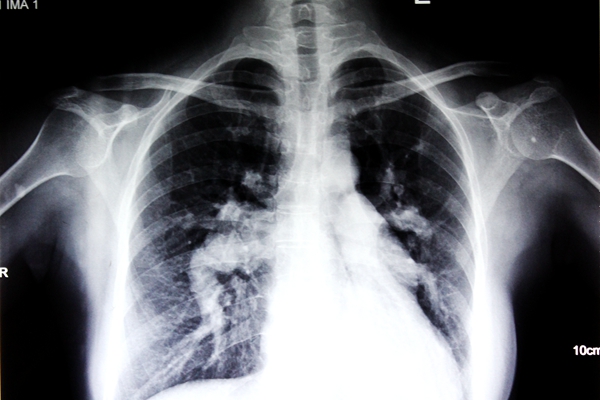

来到南宁的一家医院检查,发现邓女士的先天性心脏病-房间隔缺损已经导致肺动脉高压达到一个非常可怕的临界值,这个肺动脉高压的值再往上走,就会彻底丧失手术机会。正常的肺动脉压不超过30mmHg,平均压不超过20mmHg,邓女士的居然高达126mmHg。对于这家医院而言,邓女士的状况已经超出了他们的手术能力范围。无奈之下,邓女士只好再次踏上求医征程,经朋友介绍,来到广西中医药大学附属瑞康医院心胸外科治疗。

经过详细的心室造影和B超等各项目的检查,确定了邓女士的病情为“Ⅱ孔上腔型房间隔缺损、重度三尖瓣关闭不全、重度肺动脉高压”,瑞康医院心胸外科的专家们认为她具备手术指征,可以进行手术。在入院一个月后,经过精心的调理和周密的术前准备,邓女士顺利完成历时4个小时的手术,安返病房。